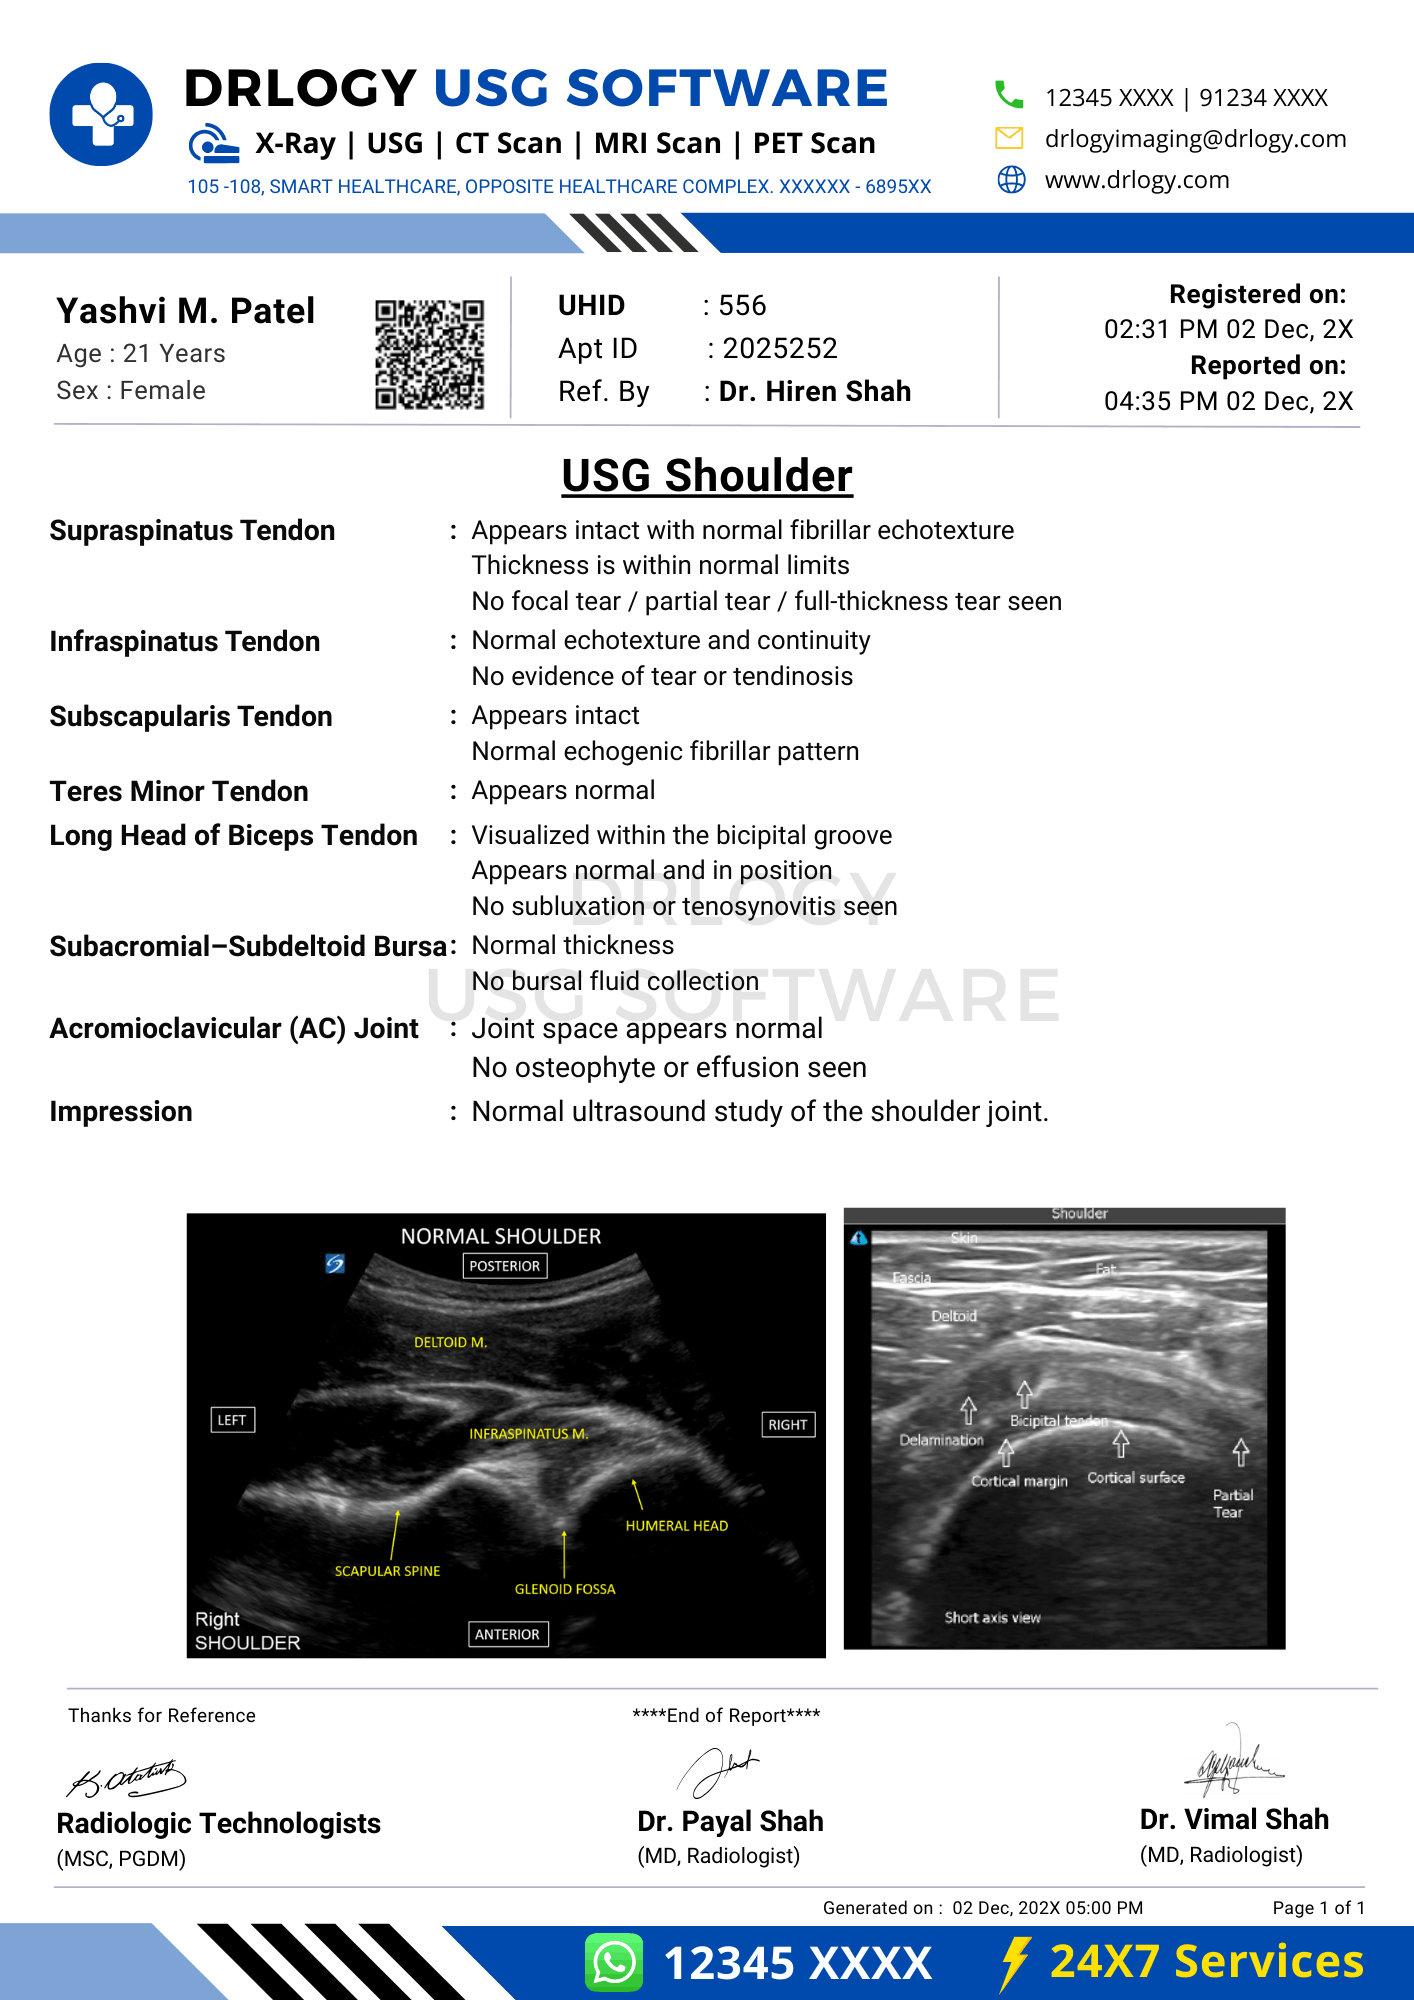

Normal USG Shoulder Report Format (Sample)

- Patient & Study Information:

- Patient: [Name], [Age]

- Study Date: [DD-MM-YYYY]

Examination: USG Shoulder

Clinical History / Indication:

Shoulder pain.

Technique / Protocol:

Ultrasound examination of the shoulder performed using high-frequency transducer.

Findings:

Biceps tendon is normally positioned within the bicipital groove. Rotator cuff tendons appear intact with normal echotexture. No bursal fluid or joint effusion is seen.

Impression / Conclusion:

No significant sonographic abnormality detected in the shoulder.

Limitations:

No significant technical limitation noted.